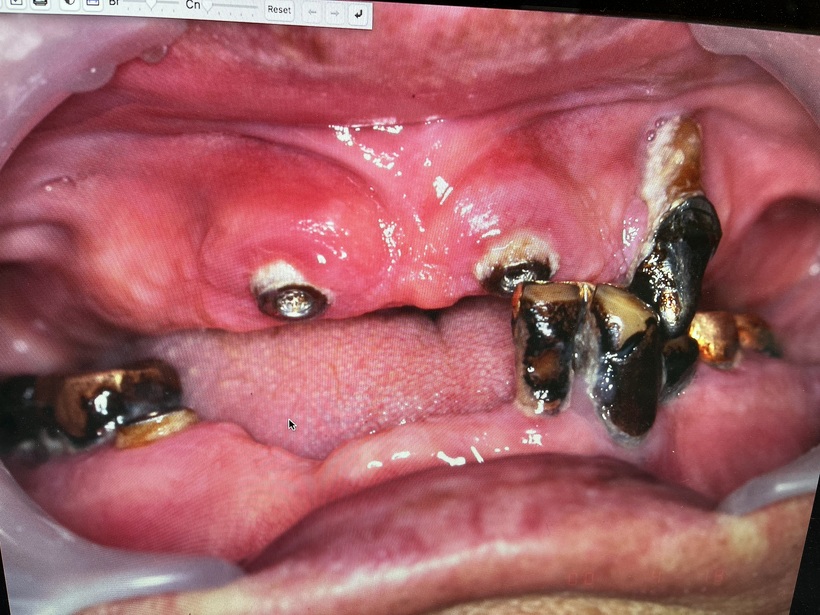

初診時 虫歯・歯周病・清掃不良